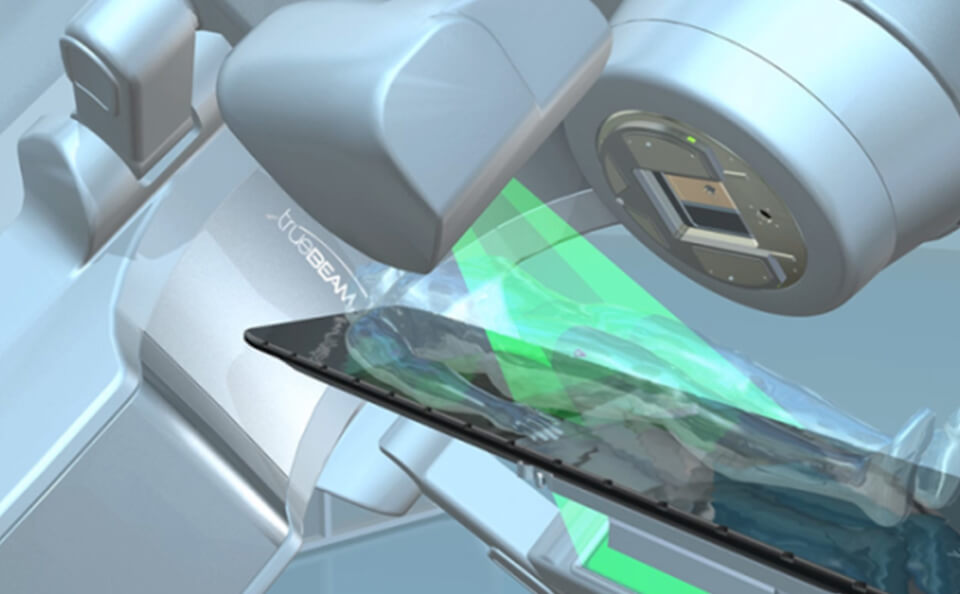

放射線治療部⾨

放射線治療とはX線や電⼦線などの放射線を病巣部に照射し、病気の治療を⾏います。また、⼿術後の再発防⽌や病気の諸症状の緩和などにも広く利⽤されます。

-

VARIAN社製 Clinac iX

VARIAN社製 Clinac iX

-

OBIによるX線撮影

OBIによるX線撮影

IGRT(画像誘導放射線治療)

治療装置に搭載されているOBI(ON BOAR IMAGE)でkV−X線画像を撮影し、その画像と治療計画CT画像から再構成された画像と位置合わせをします。また、CBCT(コーンビームCT)撮影を⾏い、照射位置微調整し位置精度を向上させます。これにより、正常な組織に放射線が当たることを最⼩限にします。

-

kV-X線画像と計画CT再構成画像との位置合わせCBCT

kV-X線画像と計画CT再構成画像との位置合わせCBCT

-

CBCT画像と計画CT画像との位置合わせ

CBCT画像と計画CT画像との位置合わせ